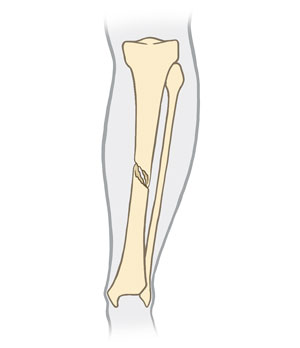

Spiral fracture

The break spirals around the bone. This is common in a twisting injury.